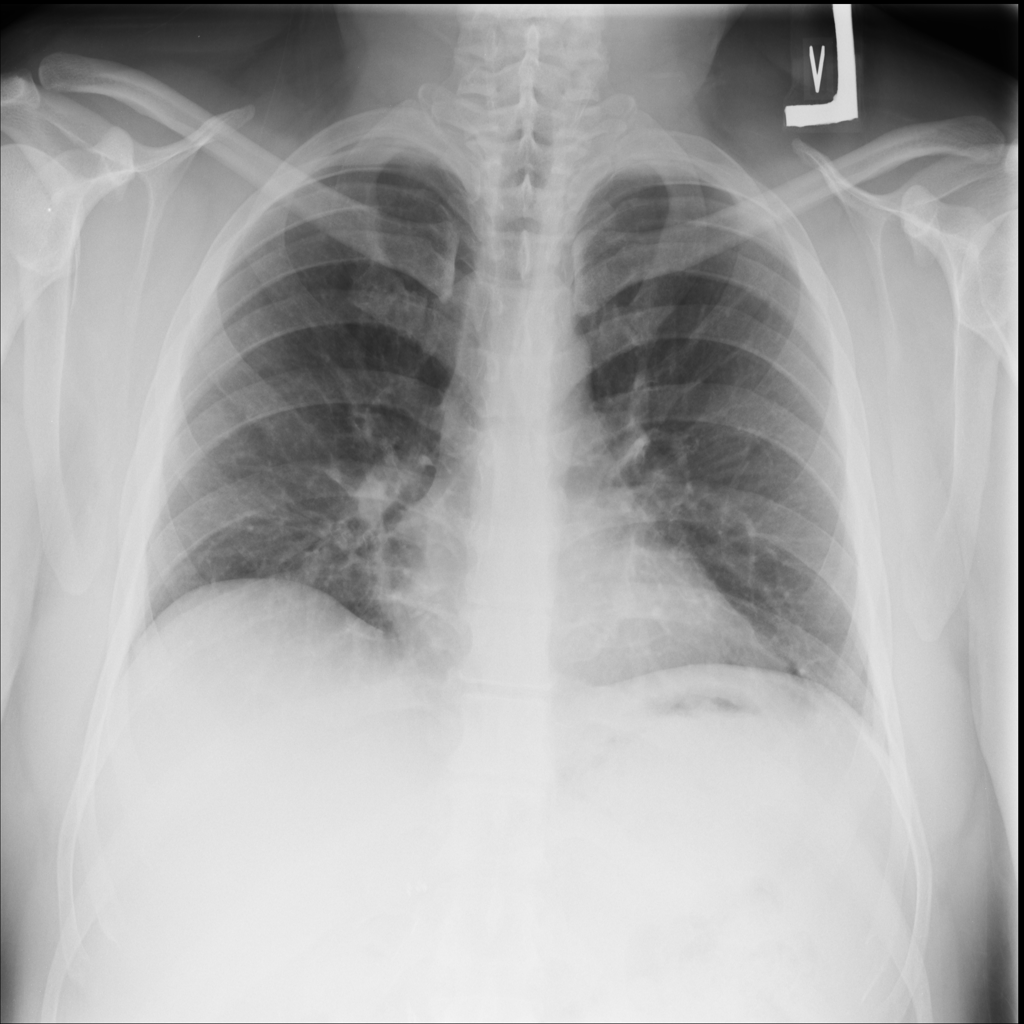

PAT-531A · IMG-006Consolidation

PAT-531A · IMG-006

PA